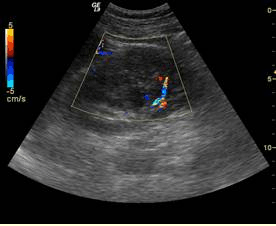

A.黄体囊肿破裂

B.急性阑尾炎

C.早期流产

D.盆腔炎性包块

E.完全性葡萄胎